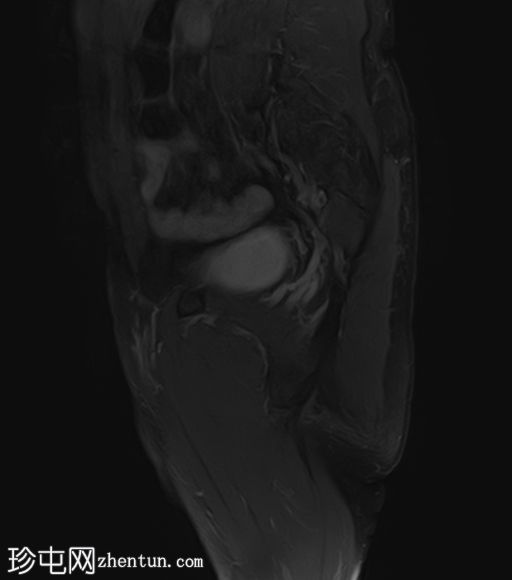

矢状位

PDFS序列

左侧股直肌近端至中段肌纤维内可见一长条状、边界清晰的肌内肿块,其大小约为:头尾径14.4 cm,横径6.6 cm,前后径2.7 cm。

该病灶在所有序列上均呈脂肪信号,T1加权像上呈高信号,脂肪抑制像上信号完全抑制(假性高信号)。

未见厚间隔、结节状结构或非脂肪成分。

MRI 显示左侧股直肌内存在脂肪瘤。

虽然 MRI 特征未提示恶性肿瘤,但体积较大、位置较深或位于下肢的病变会增加恶性肿瘤的可能性,在这种情况下,建议进行活检并开展分子检测。